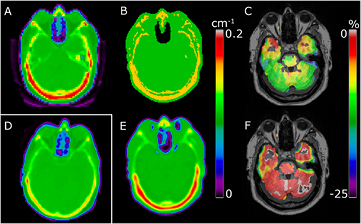

An example of the %-difference images for a patient with all the regional masks ignored, compared to application of the masks, is shown in figure 10. The error in the whole brain averaged across all patients was 2.5% (±3.1%) when ignoring all four regional masks. Compared to figure 9, the regions with errors worth noting when ignoring the regional masks were the medulla, the cerebellum, and the frontal cortex with errors of 7.0% (±4.9%), 5.9% (±5.0%), and 2.5% (±3.5%), respectively. The maximum error increased significantly in all regions compared to when applying the masks. Of note, the maximum error in the cerebellum was 22%.

Figure 10. Sample patient shown with %-difference to CT for our method without regional optimization (A) and RESOLUTE with the regional optimization (B). The areas of the regional optimization (see figures 3(A)–(D)) were manually outlined and overlaid. Notice the bias in the skull base and mastoid process causes overestimation in the cerebellum, and the bias from the frontal sinus and failure to segment the air in the nasal septa causes overestimation in the frontal lobe. The error is significantly reduced when using the regional optimization limiting the impact of the bias.

Since our method is based on the vendor-provided UTE sequence, we should assess our accuracy of PET reconstruction in the regions where the vendor-provided UTE based attenuation map is known to struggle. This is especially behind the frontal sinus and in the skull base (Keller et al 2013, Dickson et al 2014). In the averaged %-difference images we see how the 8–15% error behind the sinuses and 5–8% error in the cerebellum near the skull base, when using the UTE technique, is significantly reduced when using our method (figures 6 and 9). The improvement of using continuous bone values instead of the fixed value in UTE is clearly demonstrated in figure 8, as the probability of an error greater than ±5% near the skull is reduced from around 90% to 20% when using our method. Our segmentation of the UTE signal and assignment of continuous bone signal also seems to limit the number and extent of the outlier results, as 95% of the brain voxels are within ±10% of PETCT, compared to only 72% when using UTE (table 2).

The reduced error due to the use of RESOLUTE AC is caused by several competing effects. Firstly, RESOLUTE segments the large brain region and assigns an LAC value of 0.099 cm−1 that is lower than the vendor-provided value generally used for soft tissue (0.1 cm−1). This affects all regions in the brain. Secondly, the accurate air segmentation affects the regions near air cavities, in particular the frontal sinuses. Finally, PET AC with RESOLUTE benefits from the assignment of continuous bone values. Using a single value for bone (vendor-provided UTE, (Anazodo et al 2014)), or using an incorrect pseudo CT skull value (Burgos et al 2014, Izquierdo-Garcia et al 2014) in the MR-AC map, can in some individuals result in large regional PET errors in the brain close to the skull. This is exemplified in figure 11 where failure to compensate for the high bone density results in errors in the PET image of up to 25% in the cerebellum. Since our method is able to capture and model outlier patients with high density in the skull, this error is reduced.

Figure 11. Sample patient with high bone density. Attenuation map shown for CT (A) and UTE (B) where the fixed bone value causes underestimation of PET uptake in the brain (C) showing Δ%(PETUTE). RESOLUTE (E) is able to measure the bone density, resulting in an improved PET image (F) showing Δ%(PETRESOLUTE). Sample of normal bone density CT image from another patient shown for comparison (D).

The method by Juttukonda is, similarly to ours, based on prediction of a continuous bone value using the  signal. The method deviates from ours by the threshold for included bone. The authors use a higher threshold (550 s−1) than Keereman et al (500 s−1) (Keereman et al 2010) in order to limit the amount of fat and CSF voxels included in the bone segmentation. We chose the lower threshold of 100 s−1 since the CT values at this threshold are 200–400 HU (figure 2), representing bone, and should therefore be included to capture the full width of the skull and to avoid discontinuities. The bias at the air/tissue interfaces (figure 4) results in an overestimation of PET values when not compensated for, as shown for a sample patient (figure 10). Comparing the %-difference images shows that without the regional masks the error in the cerebellum is up to 25% regionally for this patient. This error is significantly reduced when applying our regional masks. The global mean error across all patients in the cerebellum increases from −0.9% when applying the masks, to 4.7% when ignoring the masks. Juttukonda et al proposes to use the Dixon sequence to account for the bias by segmenting the soft tissue areas where bone is unlikely to occur. We chose not to use the Dixon images due to the possibility of misregistration to UTE, the simplicity of the acquisition sequence, as well as the large voxel size. Using the Dixon images also limits the usability of the method as these have been shown to be confounded by fat–water inversion present in 8% of scans (Ladefoged et al 2014). We instead limit the bias by excluding bone from voxels with high probability of being soft tissue or brain voxels, both segmented using the UTE TE images.

signal. The method deviates from ours by the threshold for included bone. The authors use a higher threshold (550 s−1) than Keereman et al (500 s−1) (Keereman et al 2010) in order to limit the amount of fat and CSF voxels included in the bone segmentation. We chose the lower threshold of 100 s−1 since the CT values at this threshold are 200–400 HU (figure 2), representing bone, and should therefore be included to capture the full width of the skull and to avoid discontinuities. The bias at the air/tissue interfaces (figure 4) results in an overestimation of PET values when not compensated for, as shown for a sample patient (figure 10). Comparing the %-difference images shows that without the regional masks the error in the cerebellum is up to 25% regionally for this patient. This error is significantly reduced when applying our regional masks. The global mean error across all patients in the cerebellum increases from −0.9% when applying the masks, to 4.7% when ignoring the masks. Juttukonda et al proposes to use the Dixon sequence to account for the bias by segmenting the soft tissue areas where bone is unlikely to occur. We chose not to use the Dixon images due to the possibility of misregistration to UTE, the simplicity of the acquisition sequence, as well as the large voxel size. Using the Dixon images also limits the usability of the method as these have been shown to be confounded by fat–water inversion present in 8% of scans (Ladefoged et al 2014). We instead limit the bias by excluding bone from voxels with high probability of being soft tissue or brain voxels, both segmented using the UTE TE images.